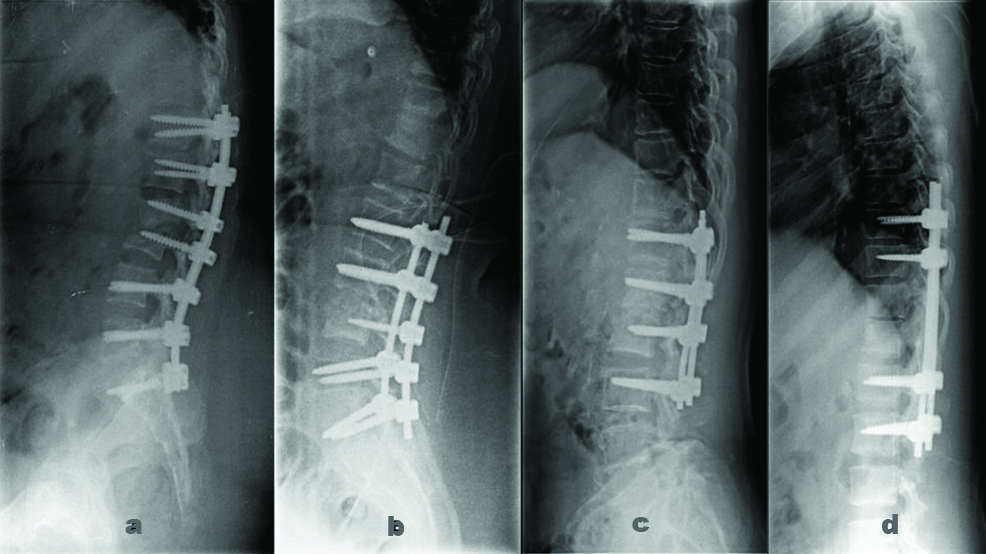

The preoperative images of the spine of all the four cases has been represented in [Table/Fig-1(a-d)]. And postoperative images of radiographic of all cases are shown in [Table/Fig-2(a-d)].

Postoperative radiographs.

a. Case 1: Lumbosacral fixation- D9-D10 to L1-L2 with pedicle screws

b. Case 2: D12-S1 fixation with pedicle screws

c. Case 3: Posterior instrumentation with pedicle screws from L1-L5

d. Case 4: Thoracolumbar fixation with pedicle screws

The patient underwent D9-D10 to L1-L2 fusion with wound debridement and posterior stabilisation [Table/Fig-2a]. The postoperative exudate was sent for routine bacteriology culture as well as Mycobacterium culture. Ziehl Neelsen (ZN) stain showed scanty AFB. The culture was positive for the Mycobacterium tuberculosis complex.

The patient was provisionally diagnosed as TB spine involving L2, L3, L4 with bilateral psoas abscess under the epidural collection. The patient was subjected to D12-S1 posterior instrumentation stabilisation with laminectomy [Table/Fig-2b]. Exudate and biopsy samples were sent for routine laboratory investigations. The culture was positive for the Mycobacterium tuberculosis complex. L2-L3 intervertebral disc biopsy was sent for histopathology examination which showed focal chronic inflammatory infiltrate with no evidence of TB.

The patient was subjected to L1-L5 posterior instrumentation and stabilisation with discectomy and fusion [Table/Fig-2c]. The tissue was sent for routine laboratory investigations. AFB culture was positive for Mycobacterium tuberculosis complex and also was confirmed by Cartridge Based Nucleic Acid Amplification Test (CBNAAT) which was sensitive to rifampicin. Histopathological Examination (HPE) of the biopsy sample from the disc showed features of acute on chronic non-specific inflammation.

The patient was clinically diagnosed with L1-L2 spondylodiscitis, Koch’s/metastasis with L5-S1 spondylolisthesis with bilateral radiculopathy. He underwent D10-S1 posterior instrumentation with stabilisation with discectomy [Table/Fig-2d]. Biopsy and exudate sample sent for routine laboratory investigations. AFB culture were positive for Mycobacterium tuberculosis complex and also were confirmed by CBNAAT which was sensitive to rifampicin. Histopathological Examination (HPE) of L3-L4 spine tissue showed caseating TB [Table/Fig-3].